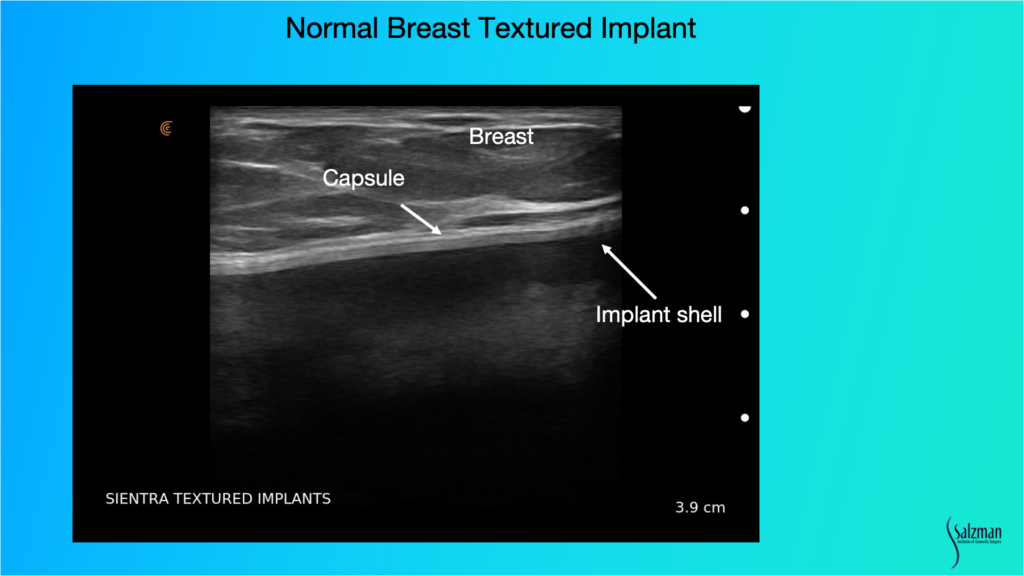

Recognizing a Normal Textured Breast Implant

When looking for pathology, we have to know what normal looks like. This is a Sientra textured implant. You can see the breast parenchyma up above where it says breast, so it’s skin, a little bit of subcutaneous fat and then the dense white breast parenchymal tissue with those little striations, which are the support structures. And then the white line that’s just underneath the parenchyma, or under the muscle if it’s a submuscular implant, is the capsule. Usually, the implant shell is a bilaminar structure. And when you look in really high definition, sometimes it will look like it has three different lines, with the fourth line being the capsule that’s just above. That’s a normal, unbroken implant.